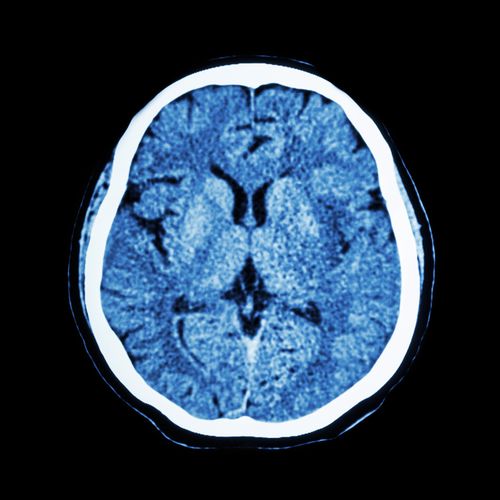

brain scan dilantin cerebral atrophyThe World Health Organization lists the seizure drug Dilantin (Phenytoin) as an essential drug for any basic healthcare system, but emerging evidence suggests that Dilantin may cause permanent changes to the brain and skull.

According to a recently published medical journal article, Dilantin may cause thickening of the skull and focal cerebral atrophy. In this condition, the skull thickens and the brain shrinks, causing a wide variety of complications.

The article detailed the case of a patient who had been diagnosed with epilepsy as a teenager and had been taking Dilantin shortly thereafter. In her 30s, the patient injured her head during a seizure and doctors took a CT scan of her brain. What they found was shocking.

The patient’s skull had visibly thickened in CT scans, and her brain had shrunk. Curiously, in this particular case, the patient did not yet suffer serious medical repercussions from the focal cerebral atrophy, and researchers described the changes as “cosmetic.”